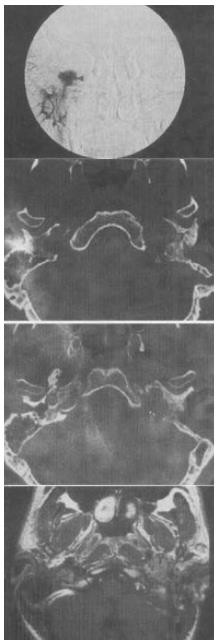

- 单项选择题 男,45岁,左侧搏动性耳鸣半年,耳镜检查透过鼓膜后下部见半膨隆紫红色肿物,CT如图,最可能的诊断是()。

- E